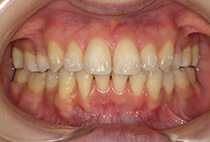

20代女性の患者さま。

八重歯の見た目が気になってご来院されましたが、実は顎の痛みや開口障害など、顎関節症の症状もありました。

八重歯が気になる

叢生、顎関節症、開口障害

治療前